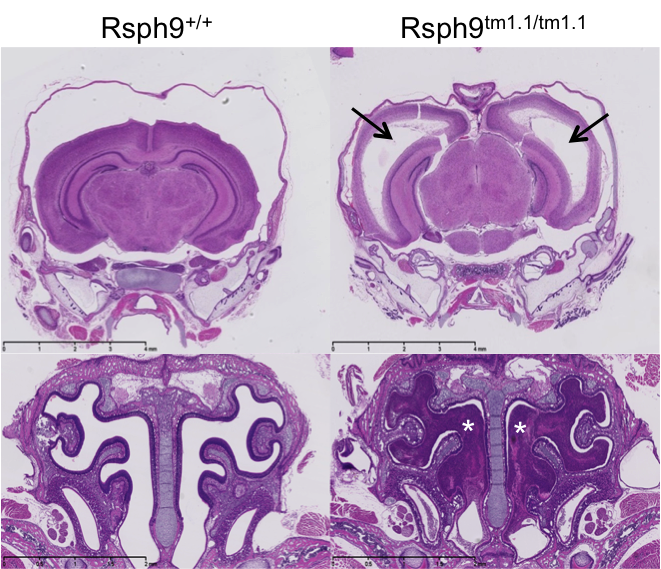

Rsph9tm1.1(KOMP)Vlcg

Radial spoke head protein 9 is a component of the radial spoke head in motile cilia and flagella. Rsph9 mutants showed partial pre-weaning lethality but viable to P7. Whole brain MRI and H&E staining of coronal sections of the P7 brain revealed severe hydrocephaly of the left and right lateral ventricles of the Rsph9 mutant. Coronal section through the nasal region showed that the sinuses of the Rsph9 mutants were filled with pus (asterisks). Both hydrocephaly and nasal blockage are phenotypes associated with Primary Ciliary Dyskinesia in humans.

H&E stained coronal sections of P7 mice revealed enlarged ventricles and blocked sinuses in the Rsph9tm1.1/tm1.1 mutant mice.